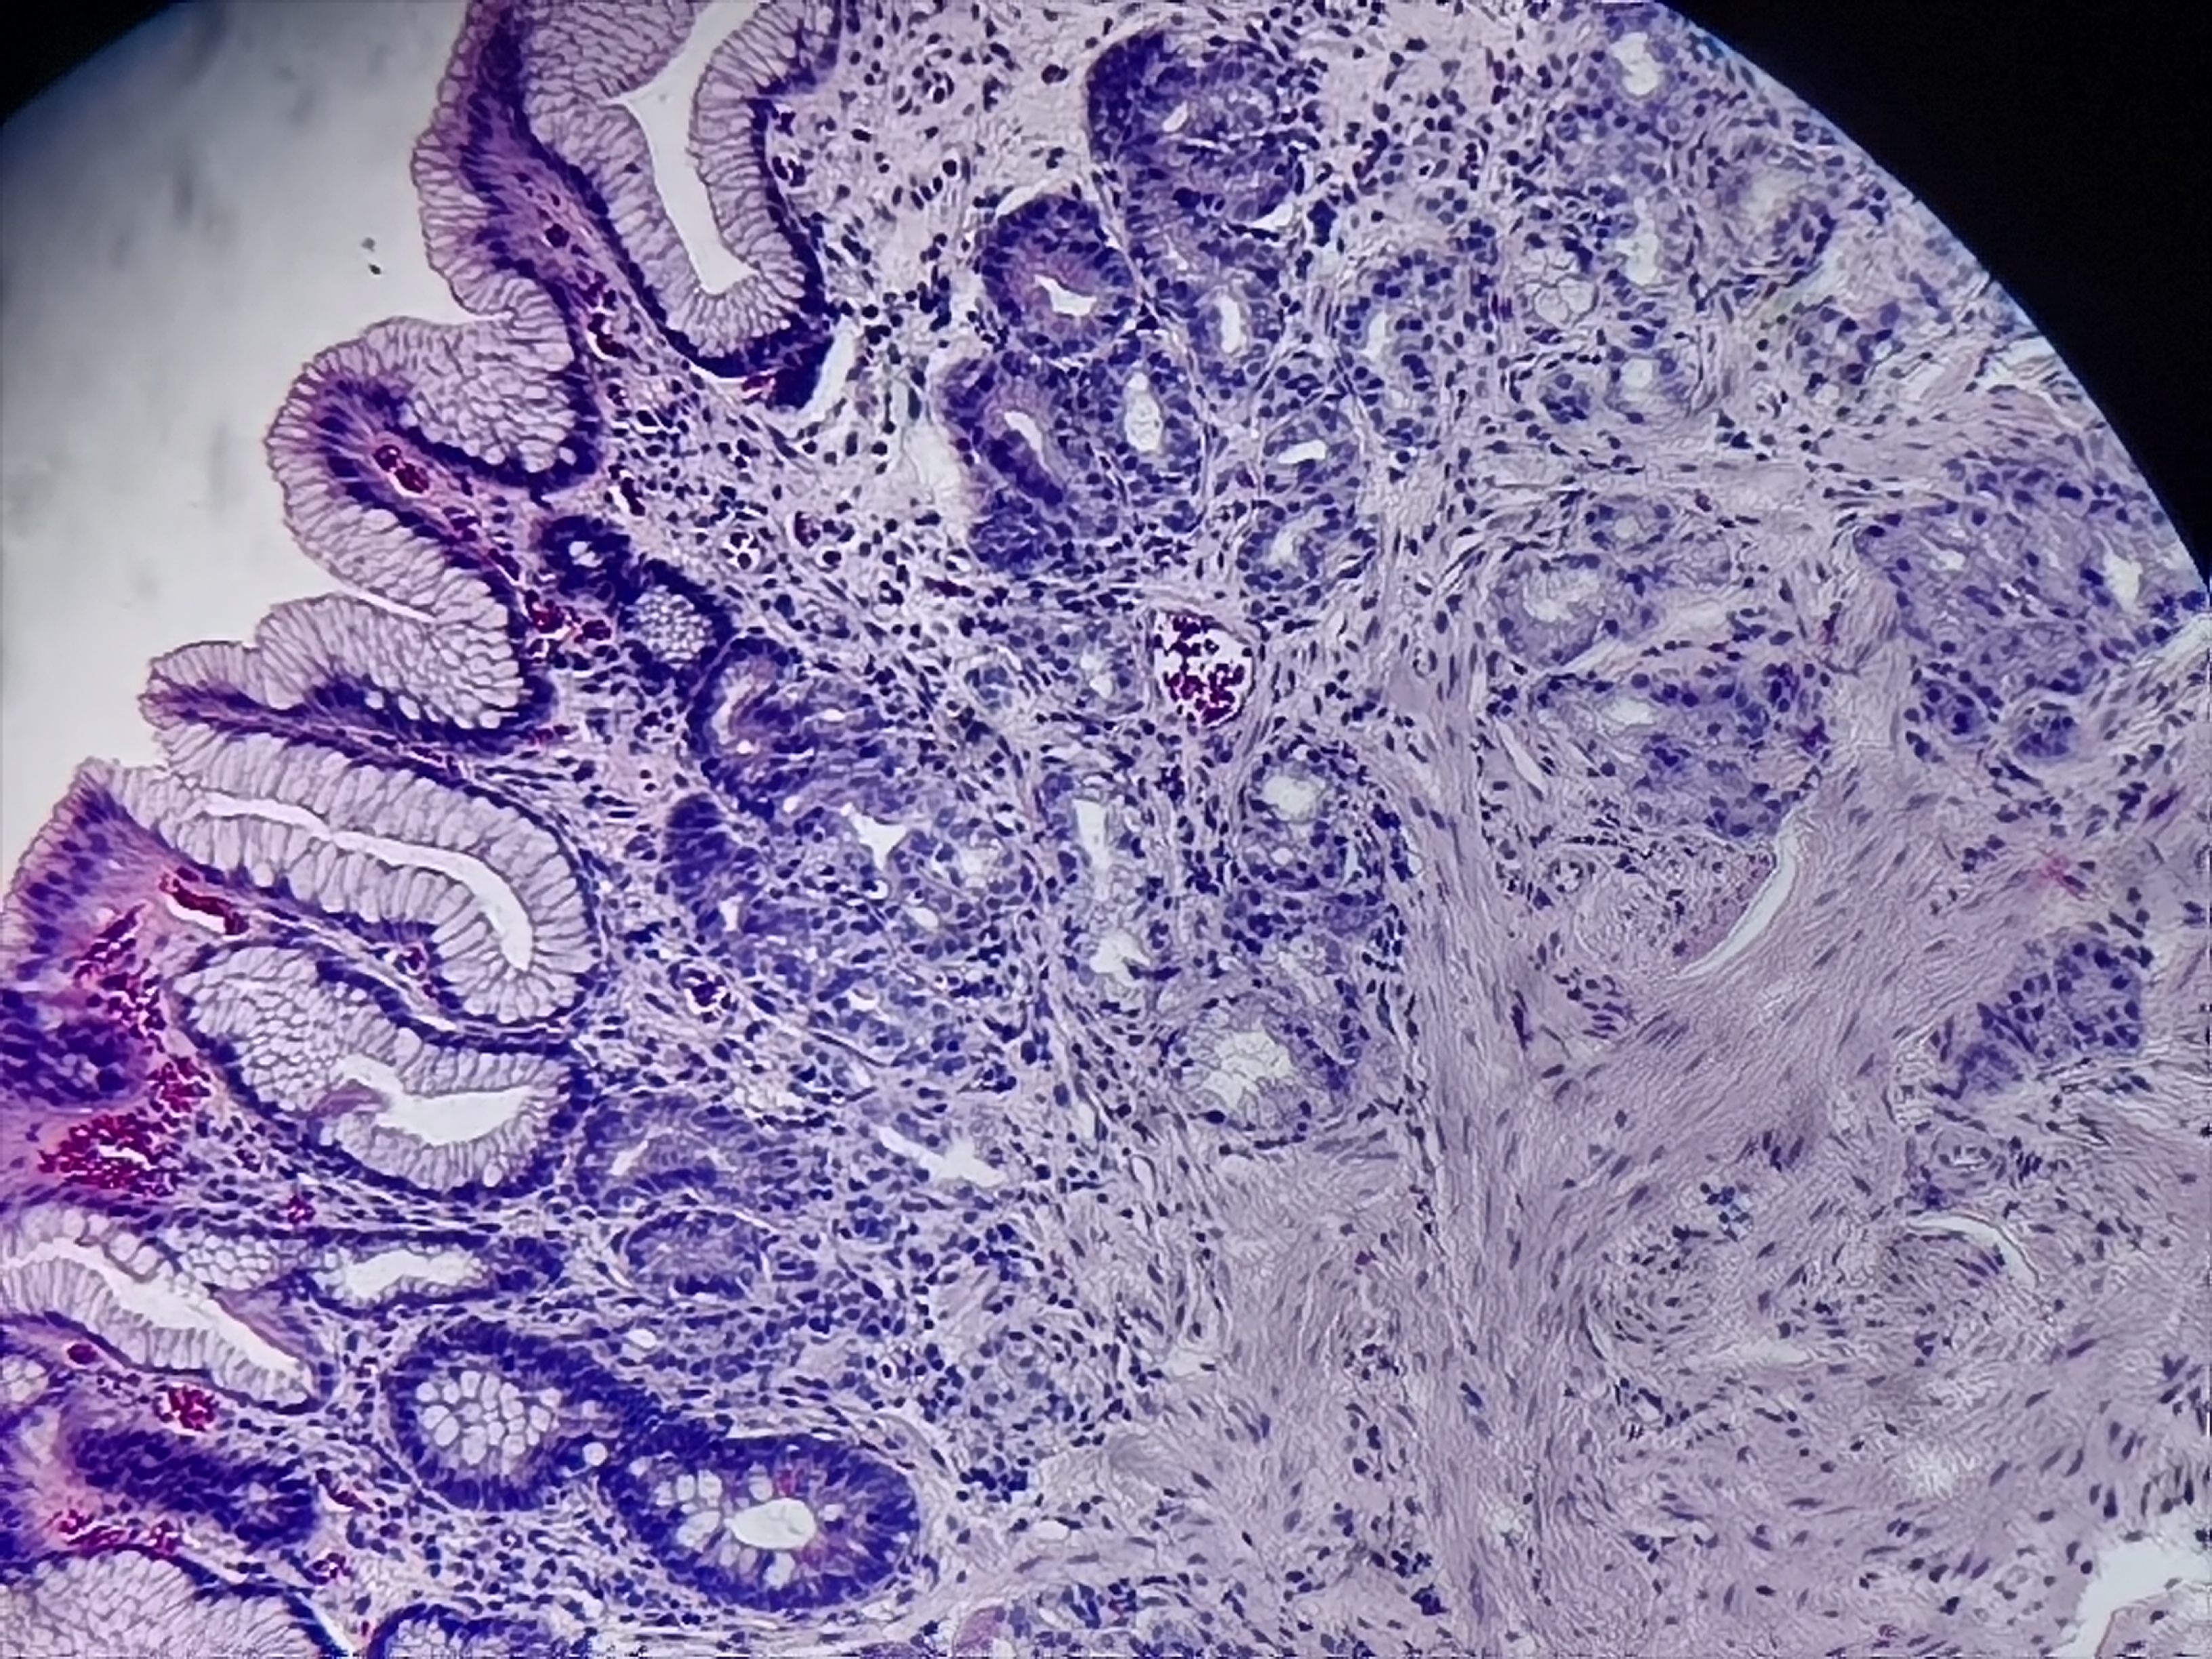

胃体活检

性别

男

年龄

58岁

临床诊断

慢性萎缩性胃炎伴糜烂

一般病史

胃体下部大弯侧粘膜凹陷

标本名称

胃体粘膜活检

大体所见

灰白色组织1块

慢性萎缩性胃炎

中度萎缩+中度肠化+糜烂